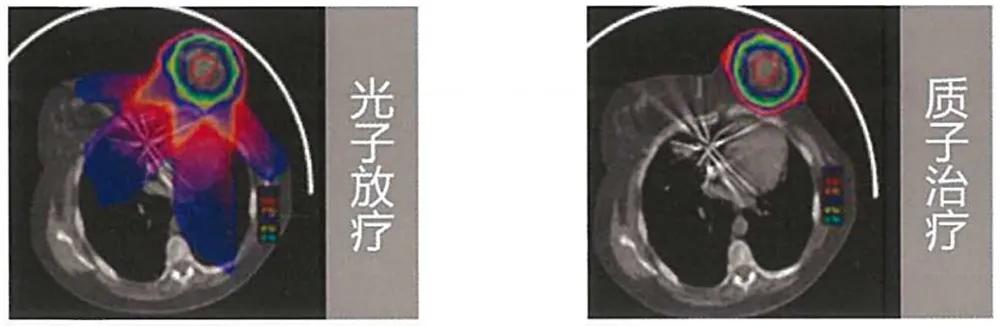

根据最新数据显示,全球肿瘤发病率以3-5%逐年增加,恶性肿瘤成为死亡原因的第一位,肿瘤患者的医疗需求逐年上升。质子治疗是当前最先进的肿瘤治疗技术,是指质子作为带正电荷的粒子,以极高的速度进入人体,在体内与正常组织或细胞发生作用的机会极低,待到达癌细胞的特定部位时,速度突然降低并停止,释放最大能量,产生Bragg峰(布拉格峰),将癌细胞杀死。相对于其他肿瘤治疗手段,质子射线的精准性对于患者正常组织的伤害更小,同时具备穿透性能强、剂量分布好、局部剂量高、旁散射少、半影小等特征。

质子治疗的极大优越性,为临床肿瘤治疗提供了使用新的治疗模式的可能,伴随粒子放疗临床技术的不断升级、放疗设备的更多应用、肿瘤患者需求不断增加,未来质子治疗将会在肿瘤放射治疗中发挥越来越大的作用。

光子放疗与质子治疗影响范围对比图(MEVION迈胜资料)